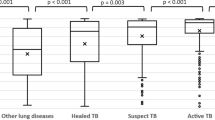

In the two facility-based ACF settings, Bangladesh and Zambia performed 24,079 and 2353 Xpert tests with a matching corresponding AI result, respectively. In the community-based ACF settings, Nigeria performed 1021 and Viet Nam performed 5074 tests. Positivity rates were 15.3% (3679/24,079) in Bangladesh, 11.6% (273/2353) in Zambia, 9.0% (455/5,074) in Viet Nam, and 8.3% (85/1021) in Nigeria (Fig. 2).

In terms of testing distribution by AI-score decile, most countries exhibited similar U-shaped patterns except Zambia (Fig. 3A). In Zambia, almost half (49.3%) of the tests were conducted in D5–D6. Meanwhile, 40.6% of Xpert tests in Bangladesh had an AI score in the lowest decile (D1), which was higher than Viet Nam (22.1%), Nigeria (17.4%), and Zambia (2.5%). Meanwhile, the testing rate in the AI-scores D4–D5, were higher in Nigeria (D4:15.3% and D5:15.0%) compared to Bangladesh (D4:4.1% and D5:3.9%) and Viet Nam (D4:5.4% and D5:5.2%).

Distribution of tests performed and test positivity across the AI-score deciles for the four countries. A Testing distribution by AI-score decile refers to the percentage of total tests performed within each AI-score decile. B Test positivity by AI-score decile shows the proportion of positive results in each AI-score decile. The decile labels (D1 to D10) represent AI-score deciles; D1–D10 for 0–0.99 in 0.1 intervals for qXR score and D1–D10 for 0–99 in 10-point intervals for CAD4TB score

In terms of positivity by AI-score decile (Fig. 3B), the two facility-based ACF sites exhibited higher rates than the community-based counterparts. In Bangladesh, positivity was higher in the high AI-score deciles of D7–D10 than in the other countries, with rates increasing from 12.3 to 70.0%. Zambia exhibited a similar pattern with a lower peak with rates, ranging from 13.6 to 65.1% for D7 and D10, respectively. In comparison, the respective positivity of D7 and D10 only rose from 4.8 to 28.7% in Nigeria and from 6.3 to 30.6% in Viet Nam.